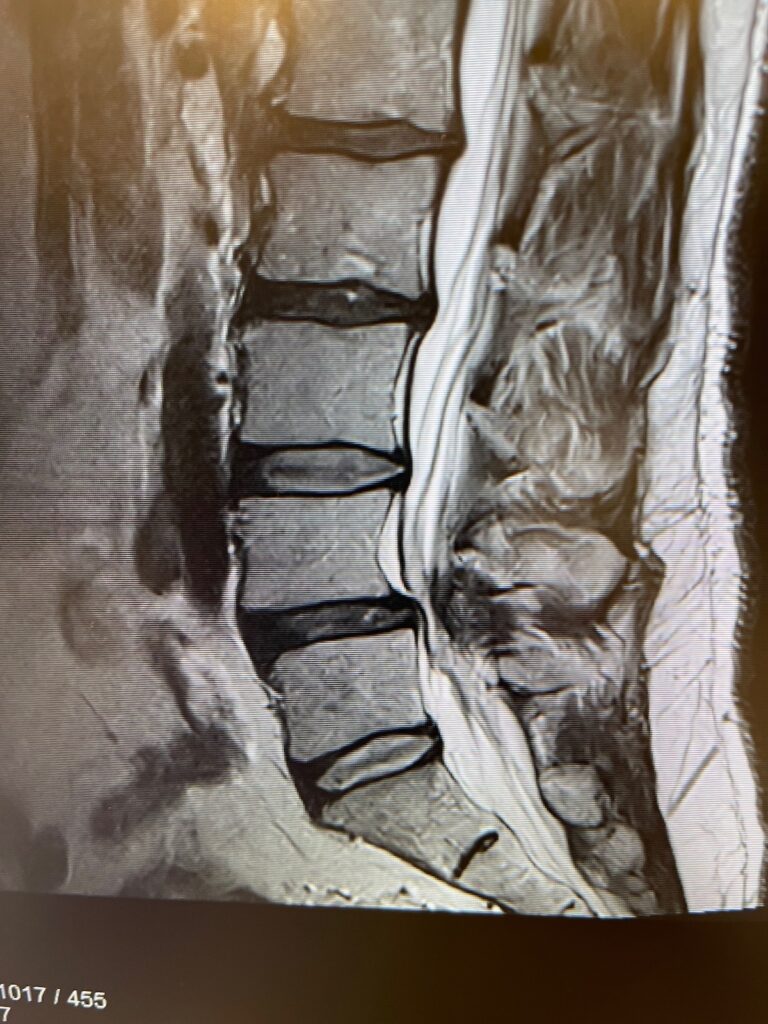

360° Minimally Invasive Fusion for Spondylolisthesis in an Outpatient Setting

This patient underwent a 360° minimally invasive spinal fusion (MISS) to treat spondylolisthesis—performed entirely in an ambulatory surgery center. Traditionally, this type of procedure requires hospitalization and an extended recovery period. However, by leveraging advanced minimally invasive techniques, Dr. Peloza was able to perform the fusion with minimal disruption to tissue and surrounding structures.